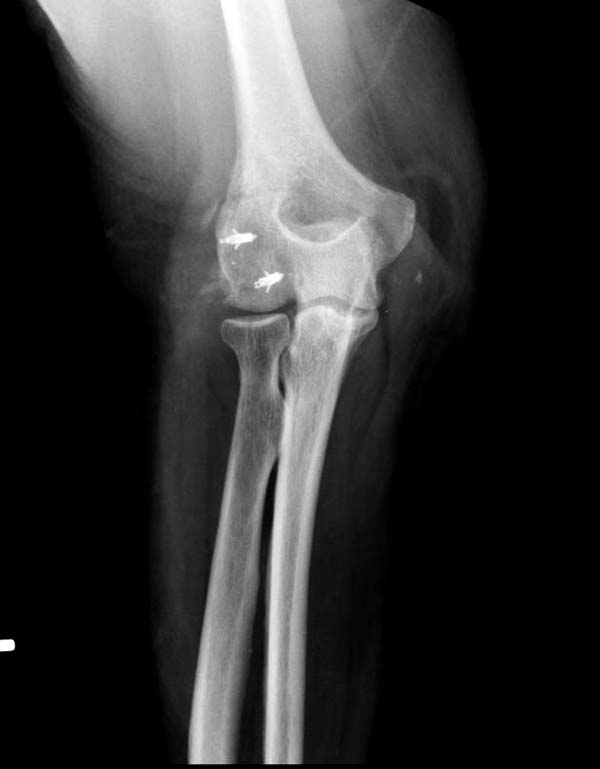

В данном случае имеется, так называемая, "ужасная триада" локтевого сустава, включающая перелом головки лучевой кости, перелом венечного отростка и вывих костей предплечья кзади, также в структуру травмы входит повреждение латерального коллатерального связочного комплекса и возможно передней порции медиальной коллатеральной связки. Лечение состоит из следующих этапов: фиксация венечного отростка( анкер или проволочная петля типа лассо), далее остеосинтез или протезирование головки лучевой кости ( КТ было бы желательно, фотографии не особо четкие), затем шов латерального коллатерального связочного комплекса. Если сохранится нестабильность, потребуется или шов передней порции медиальной коллатеральной связки с иммобилизацией верхней конечности аппаратом внешней фиксации (желательно с сохранением движений в локтевом суставе) или только аппарат(мнения расходятся). Аппарат 6 недель. Результаты лечения таких повреждений не очень хорошие.

Для примера здесь случай начатый в другом центре, а потом переправленный к нам.

Снимки: 1-2 вывих, 4-5 вторичное смещение в гипсе, реконструкция латеральной связки и капсулы 13-14, повторный вывих после реконструкции, перевод в наш центр; 18-21 временная фиксация, 22-25 трансартикулярная фиксация и нестабильная головка фиксирована спицами, 29-30 амбулаторно, 32-33 после удаления винта и спиц...